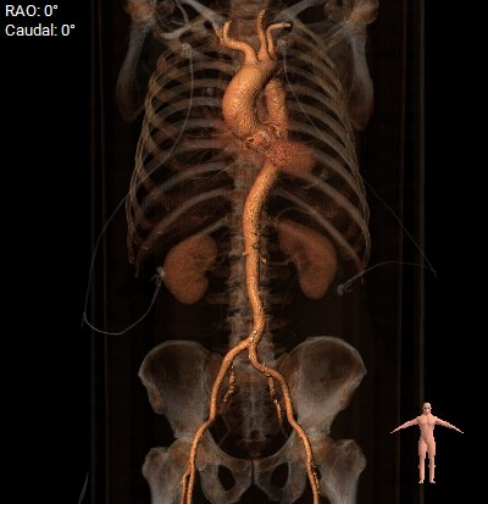

CT分析:

术前CT分析判断该心耳为反鸡翅型左心耳,选择偏下略偏前的位置进行房间隔穿刺。在工作体位造影后,可见左心耳内梳状肌发达,反鸡翅叶显影清晰,鞘管轴向佳。经DSA测量左心耳开口18mm深度17mm,结合TEE测量数据,综合考虑选用WATCHMAN24mm封堵器进行封堵。在展开封堵器时利用在体内借深度技巧,保证封堵器封堵位置合理。封堵器展开后经造影检查封堵器封堵效果理想,牵拉试验稳定。超声评估封堵器各角度无残余分流,位置理想,满足PASS原则,随即释放封堵器,一站式手术顺利结束。